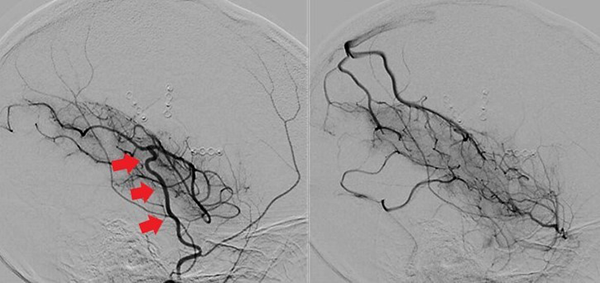

Caso clínico #3 (cirugía bilateral): GM femenino de 27 años, con antecedente de hipotiroidismo secundario a Enfermedad de Hashimoto; consultó por cuadro de parestesias y paresia leve braquial izquierda de más de 6 meses de evolución. La RMN evidencia pequeñas imágenes isquémicas en ambos centros semiovales a predominio derecho; la ARM y ADC muestran la estenosis severa de ambas arterias carótidas internas y ausencia del origen de ambas arterias silvianas con vasos de MM presentes; corresponde a un grado 3 de Suzuki (Fig. 6). Se realizó primero un bpTS derecho más EDMS y, a los 10 meses, otro bpTS más EDMS izquierdo con buena evolución en ambas revascularizaciones. La ADC alejada muestra franca mejoría de la perfusión cerebral bilateral más marcado a la izquierda (Fig. 7 y 8).

Fig. 6 Caso clínico #3. Preoperatorio. A la izquierda, la RMN evidencia pequeñas imágenes isquémicas en ambos centros semiovales mayor a derecha, la ADC muestran la estenosis severa de ambas arterias carótidas internas supraclinoidea y ausencia del origen de ambas arterias silvianas, vasos de MM presentes correspondiente a un grado 3 de Suzuki

Fig. 7 Caso clínico #3. Postoperatorio. ADC lado derecho que muestra buena perfusión cerebral del bpTS (las flechas rojas muestran el curso de la aTS) y la EMDS

Fig. 8 Caso clínico #3. Postoperatorio. ADC lado izquierdo con muy buena perfusión cerebral desde el bpTS (las flechas rojas muestran el curso de la aTS) y la EMDS